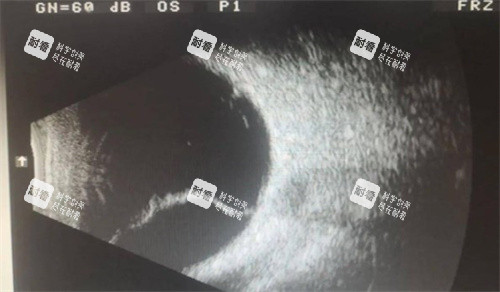

視網(wǎng)膜脫落是一種重的影響視力的眼部疾病,通常需要通過手術(shù)進(jìn)行治療。許多患者在面臨視網(wǎng)膜脫落手術(shù)時(shí),都會(huì)關(guān)心手術(shù)的費(fèi)用問題。本文將詳細(xì)為大家介紹視網(wǎng)膜脫落手術(shù)的收費(fèi)情況。

術(shù)前需要進(jìn)行一系列的檢查,如眼部超聲、眼底照相、眼壓測量等,以確定視網(wǎng)膜脫落的情況和患者的眼部整體狀況。這些檢查費(fèi)用大約在 1000 - 2000 元左右。

除了與鞏膜扣帶術(shù)相同的檢查項(xiàng)目外,可能還需要進(jìn)行一些更詳細(xì)的檢查,如光學(xué)相干斷層掃描(OCT)等,以更比較準(zhǔn)地了解視網(wǎng)膜的情況。術(shù)前檢查費(fèi)大約在 1500 - 2500 元左右。